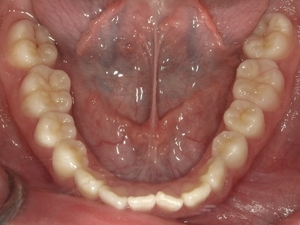

〇ご相談内容:歯のねじれが少し気になる〇矯正の種類:マウスピース型矯正「インビザライン」〇治療期間:14週間〇治療費用:44万円(税込)